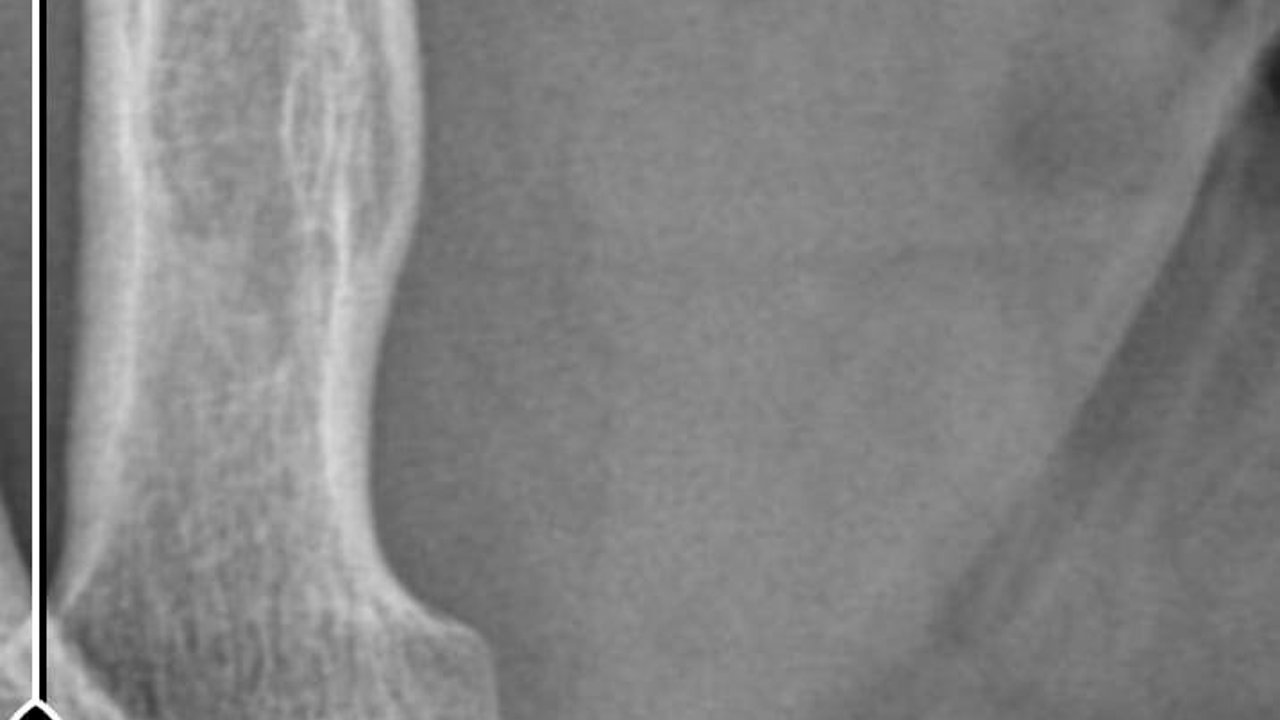

1 SANTİMETRE METAL PARÇA TESPİT EDİLDİ

Nurettin Güleryüz, ampütasyon sonrası sağ kolunda ağrı ve şişlik şikayetleri yaşayınca Darıca Farabi Eğitim ve Araştırma Hastanesi'ne başvurdu. Burada yapılan tetkiklerde, Güleryüz'ün kolunda 14 milimetre boyutunda yabancı cisim bulundu. Marmara Üniversitesi Pendik Eğitim ve Araştırma Hastanesi'nde düzenlenen epikriz formunda ise sağ kol dirsek üzerinde yaklaşık 1 santimetre metal parçaya rastlandığı belirtildi. 9 aydır çalışamadığını belirten Nurettin Güleryüz, iki özel hastane hakkında avukatı aracılığıyla savcılığa suç duyurusunda bulundu. Öte yandan Güleryüz'ün, kolunda tespit edilen metal cismin çıkarılması için Darıca Farabi Eğitim ve Araştırma Hastanesi'nde ameliyata alınacak.